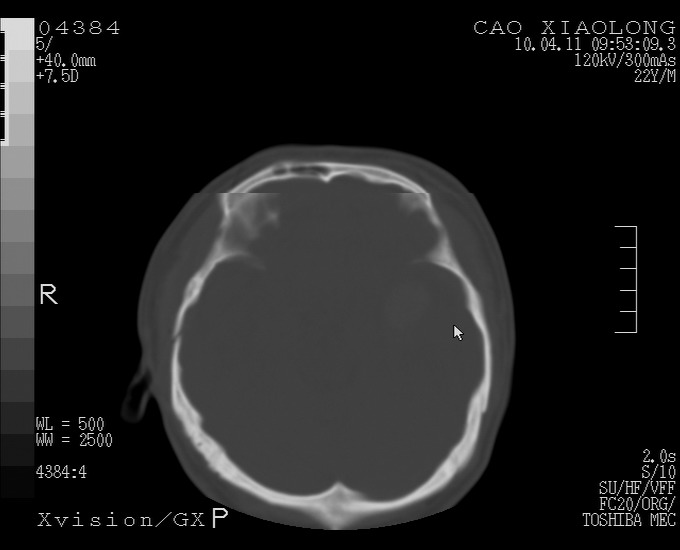

以下是引用随光逐影在2010-4-11 11:00:00的发言:[br]1)左侧额颞顶部硬膜下血肿。2)蛛网膜下腔出血。3)右侧颞顶部颅骨线形骨折。[br][br]20小时后复查:左侧额颞叶脑挫裂伤;左侧额颞顶部硬膜下血肿及蛛网膜下腔出血有吸收表现;右侧颞顶部颅骨线形骨折。[br]